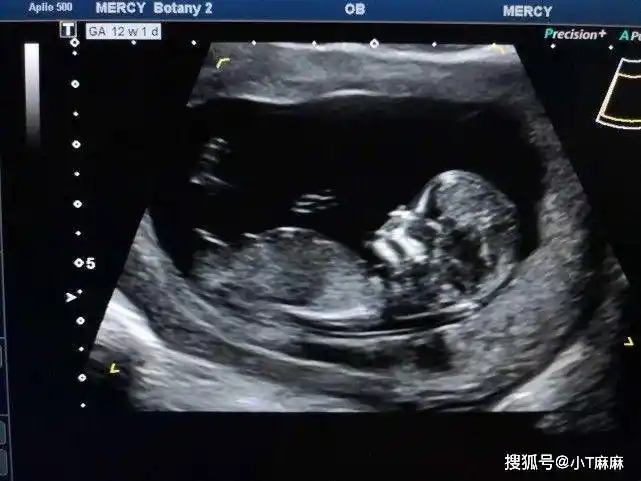

b超检测胎儿颈后透明层厚度nt检查 早期唐氏筛查填写表格,拿到母子